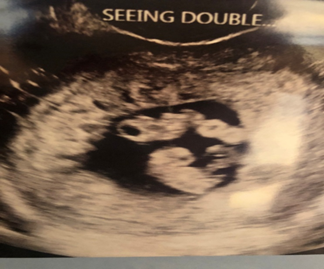

“Wait! Are there two?!”

“Yes.”

At that first appointment they determined that our boys were identical. Adam

and I sat there in awe that they could tell that right away. They could see the

thin membrane separating our two boys and the one placenta they shared, making

them monochorionic diamniotic twins, AKA mono/di twins. They had separate

sacks, but a shared placenta. Fraternal twins do not share a placenta